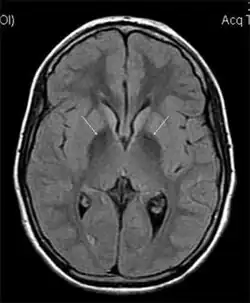

MRI hypointensity (white arrows) in the globus pallidi that indicates the presence of iron deficiencies which would be seen in a diagnosis of Aceruloplasminemia

Diagnosis of this disorder depends on blood tests demonstrating the absence of serum ceruloplasmin, combined with low serum copper concentration, low serum iron concentration, high serum ferritin concentration, or increased hepatic iron concentration. MRI scans can also confirm a diagnosis; abnormal low intensities can indicate iron accumulation in the brain.[5]